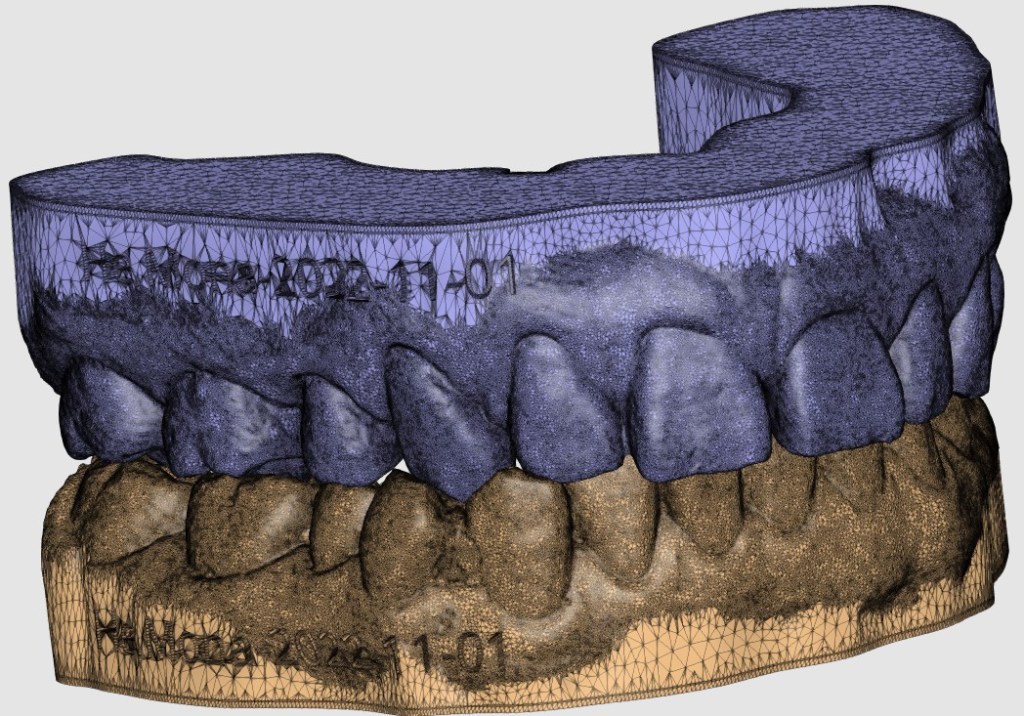

Mona H. – Missing tooth Collapse with Cross Bite Correction – Age 44 Adult Orthodontics